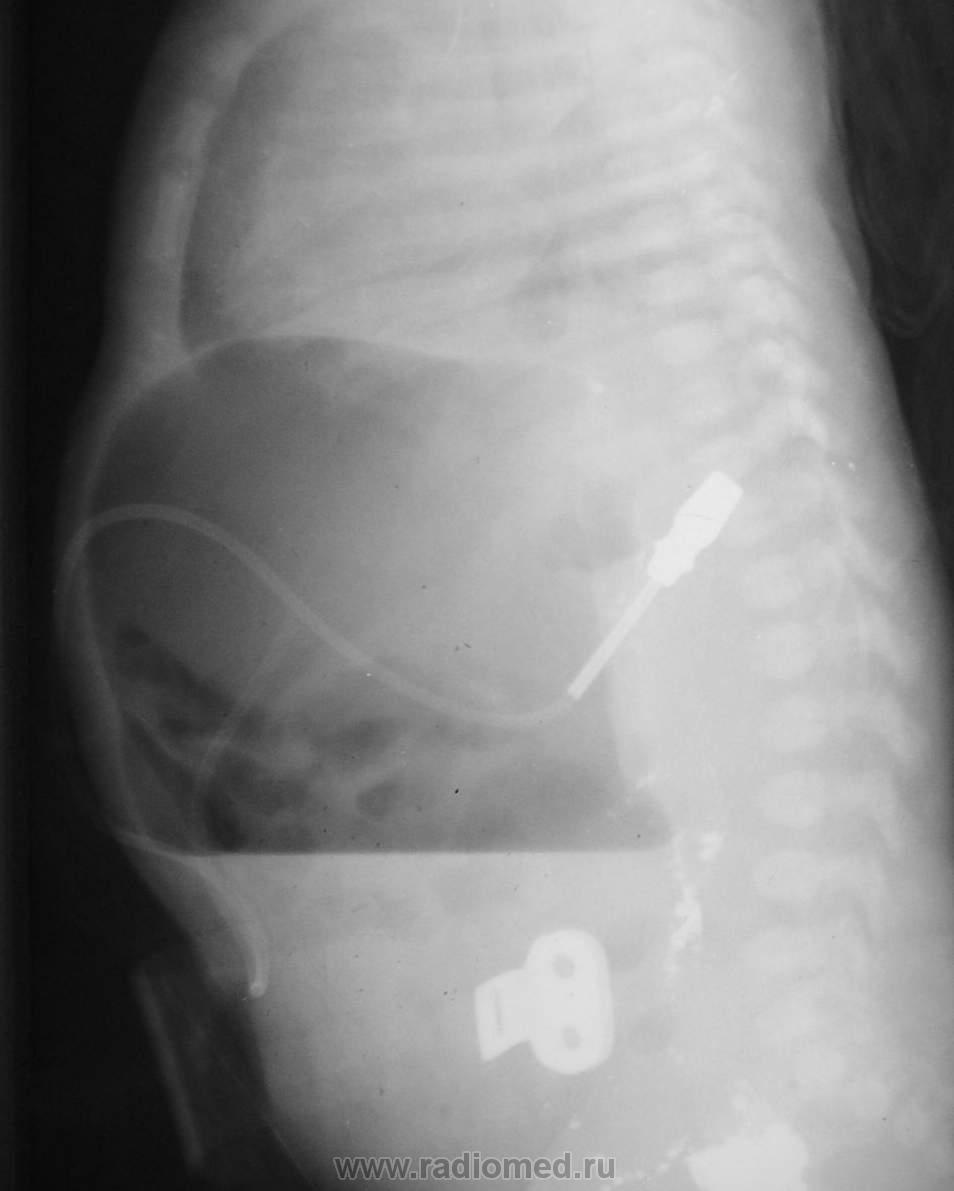

Снимки при поступлении. Клиника кишечной непроходимости. Что делали раньше из направления непонятно. Ваше мнение?

Газовый пузырь один. Второго в 12 п кишке не видно. Следы бария, не пойму где, вроде не в желудке. Может пилостеноз. Что за трубочки, не знаю.

С атрезией погорячилась, газ-то дальше есть в кишке. Признаков инвагинации не вижу. Барий в 12-п.к в тазу? На боковом снимке по задней стенке желудка непонятная плоская площадка, никогда такого не видела. Очень интересно узнать, что же это такое.

Только сейчас заметила: "клиника инвагинации"! Неужели неудачная попытка распраить?! Это растянутая подвздошная кишка?

На момент производства рентгенограмм - картина перфорации кишечника, газ и жидкость в свободной  брюшной полости. Ребенок немедленно взят в операционную, на операции инвагинация тонкой кишки в толстую, вовремя нераспознанная, с некрозом, разрывом кишечника, каловым перитонитом. Спасти ребенка не удалось...

Странно, почему нет свободного газа под правым куполом? Сколько видел перфораций, печень висела вдоль позвоночника, и газ везде (правда, это у новорожденных)

Здравствуйте. Если чесно, мне самому не все ясно в данном наблюдении, но что имеем, то имеем.  Контрастное вещество - вероятно не барий а йодлипол, куда и зачем он был введен на предыдущих этапах исследования не совсем понятно. Катетер, судя по снимкам - в брюшной полости. Остальные подробности уже не вспомнить - около 20 лет назад...